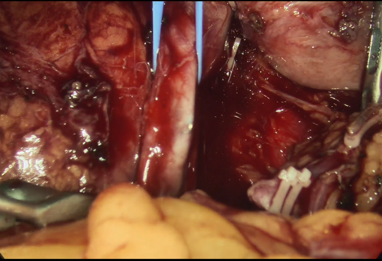

图为:全麻下开腹下腔静脉切开滤器取出术